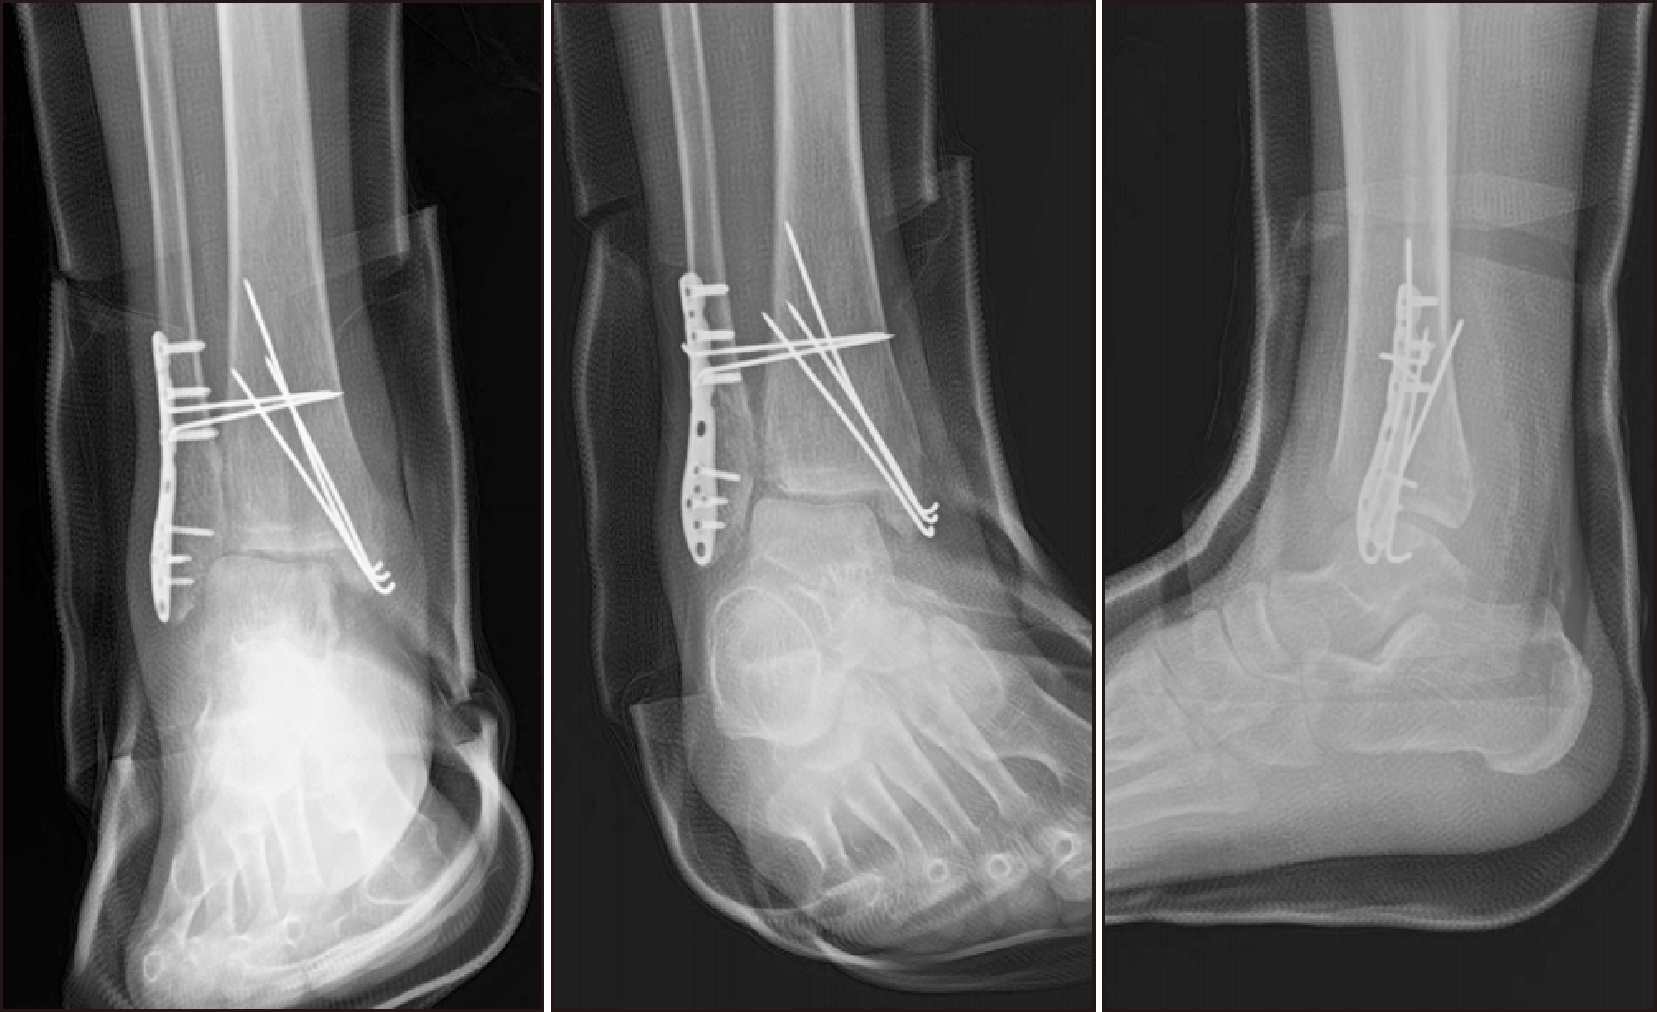

Subsequent imaging studies revealed non-union and lateral displacement of the fractures, prompting a revision OR/IF. The patient was also placed in isolation due to COVID-19, and further radiographs revealed metal failure and tibiotalar joint dislocation (Fig. 5). An implant-associated infection was confirmed, leading to subsequent procedures including metal removal, debridement, and the application of an external fixator (Fig. 6).

Figure 5

(A) Five weeks post-surgery, radiograph confirming non-union and lateral displacement of the fractures. (B) Findings of metal failure and tibiotalar joint dislocation observed during COVID-19 isolation.

Figure 6

(A) Post-operative radiograph after applying external fixator for septic ankle findings. (B) Intra-operative clinical picture applying external fixator for septic ankle findings.